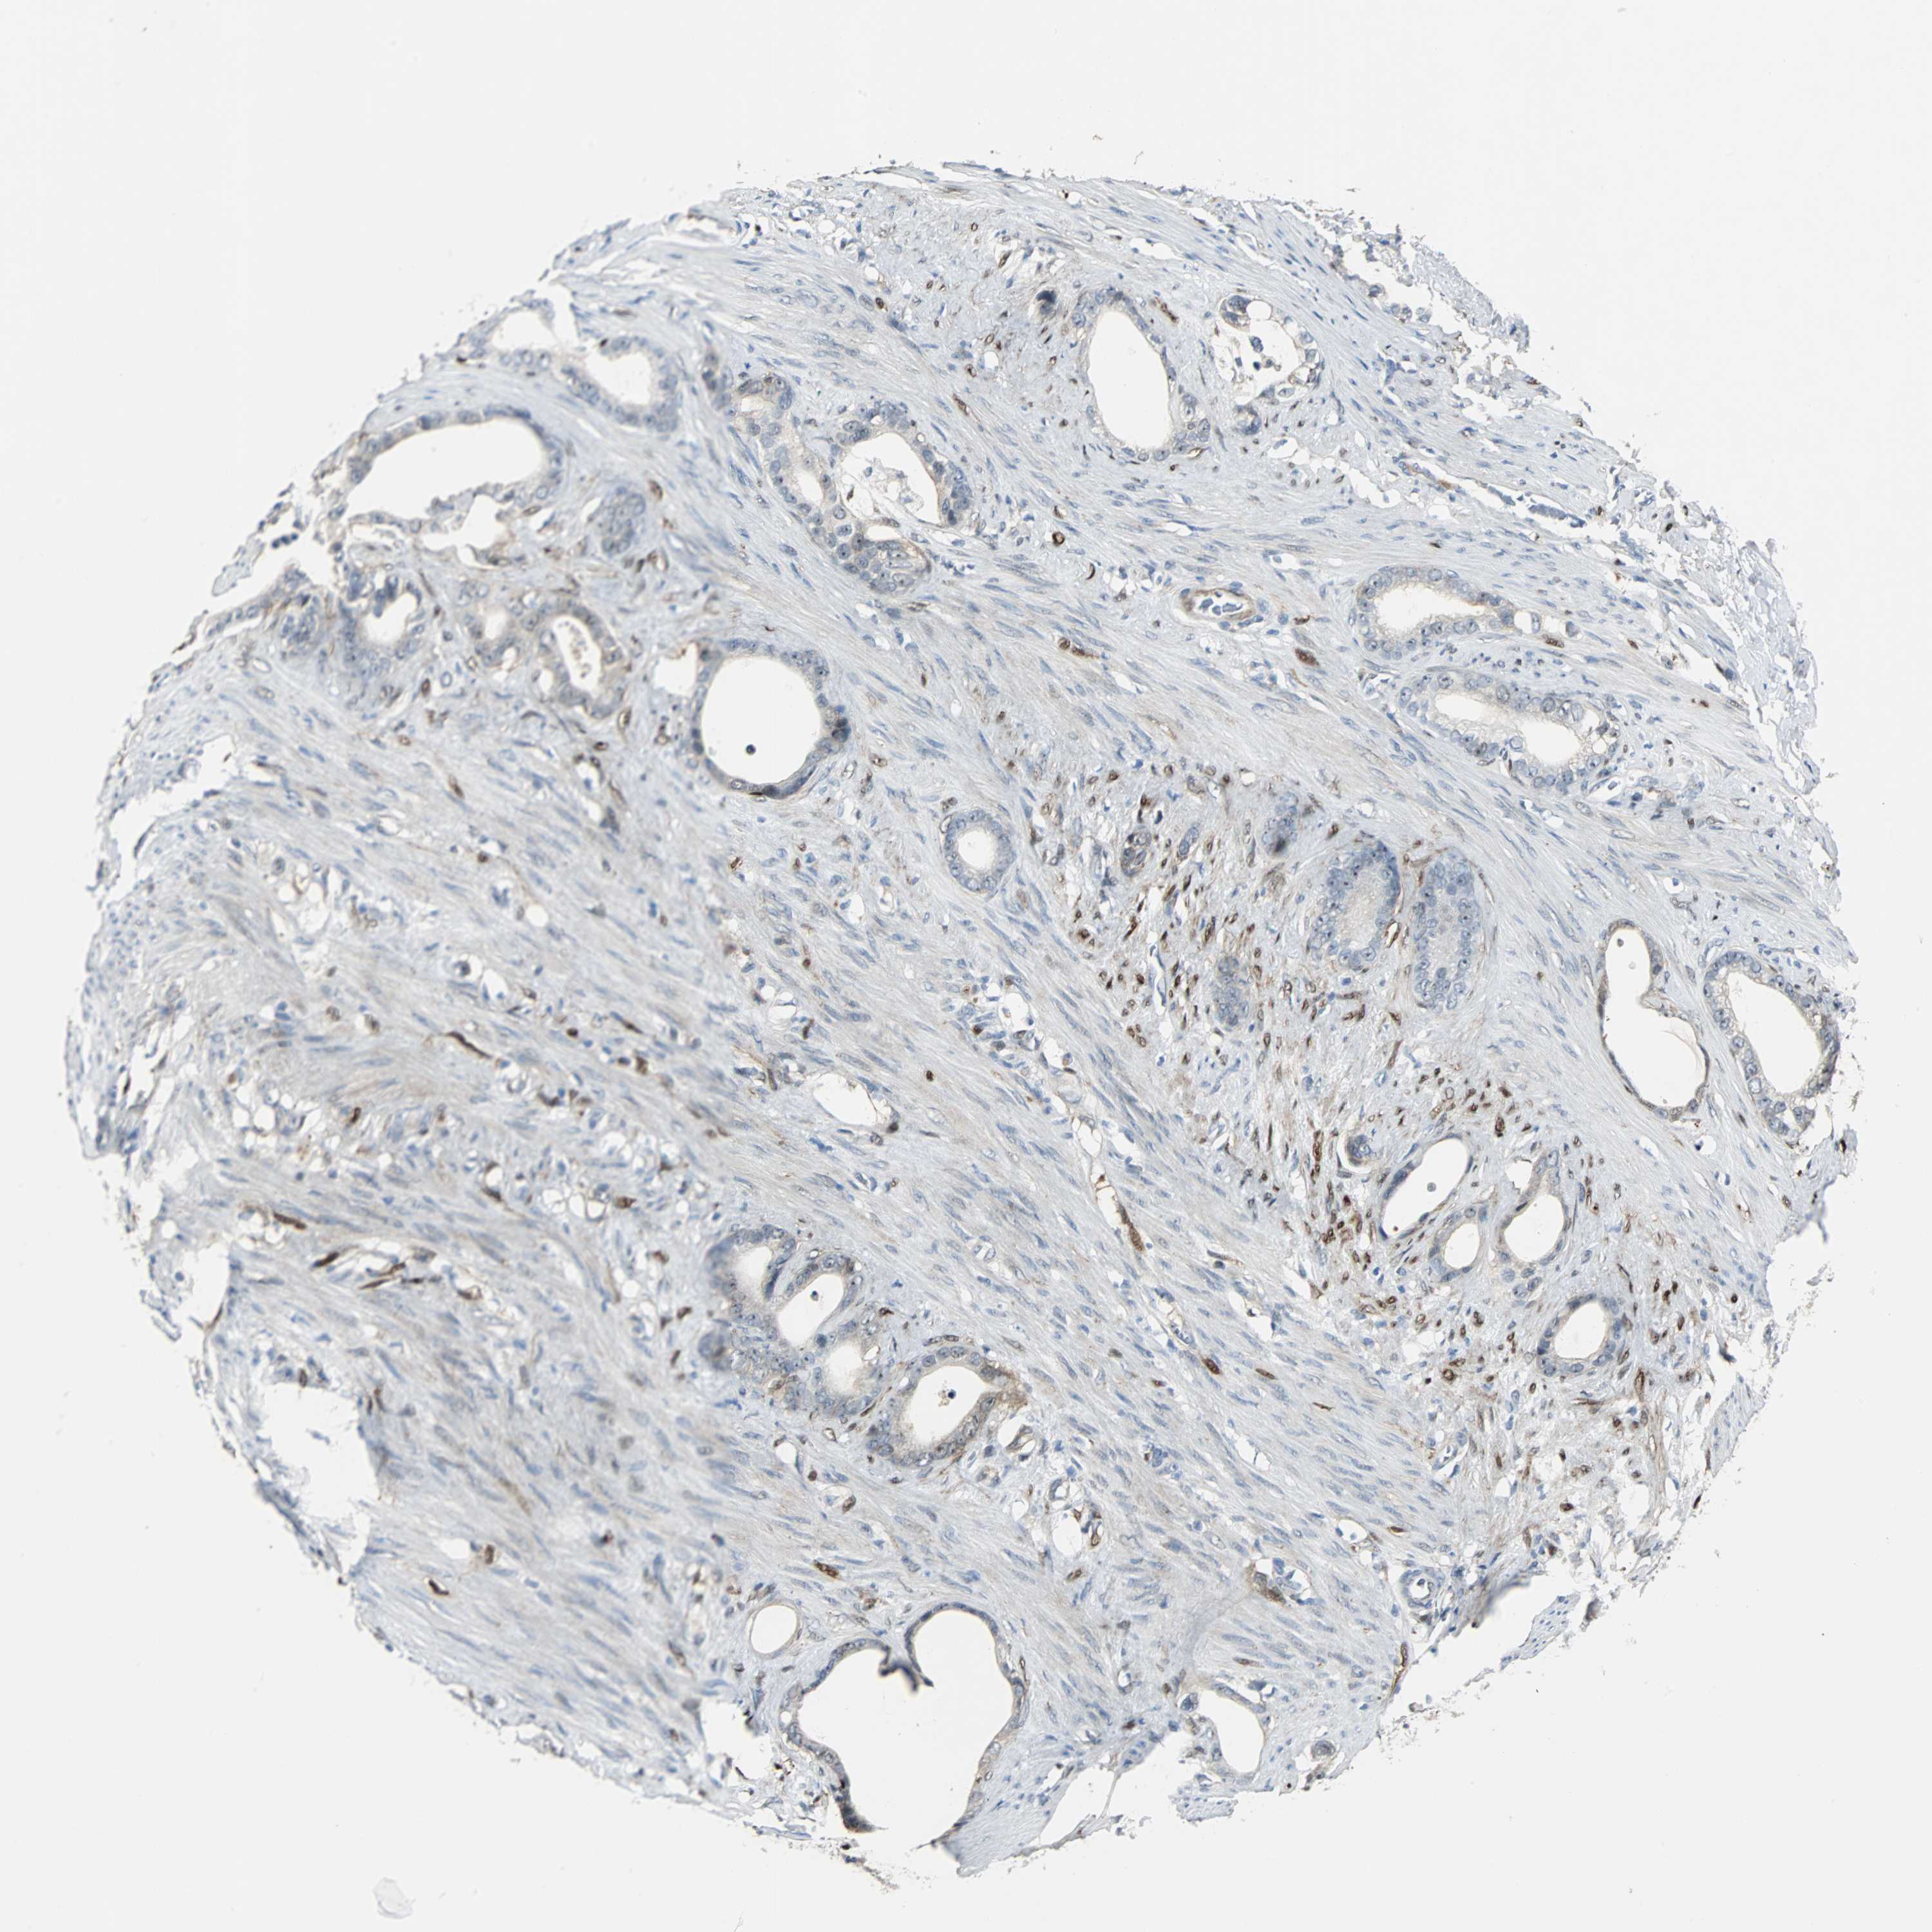

STOMACH CANCER - Protein expressioni

A mouse-over function shows sample information and annotation data. Click on an image to view it in a full screen mode. Samples can be filtered based on level of antibody staining by selecting one or several of the following categories: high, medium, low and not detected. The assay and annotation is described here.

Antibody stainingi

Antibody staining in the annotated cell types in the current human tissue is reported as not detected, low, medium, or high, based on conventional immunohistochemistry profiling in selected tissues. This score is based on the combination of the staining intensity and fraction of stained cells.

Each image is clickable and will lead to virtual microscopy that enables deeper exploration of all samples and also displays staining intensity scores, fraction scores and subcellular localization as well as patient and tissue information for each sample.

Antibody HPA005922

Antibody HPA006028

Antibody CAB008368

Staining

High

Medium

Low

Not detected

Intensity

Strong

Moderate

Weak

Negative

Quantity

>75%

75%-25%

<25%

None

Location

Nuclear

Cytoplasmic/membranous

Cytoplasmic/membranous,nuclear

Adenocarcinoma, NOS

Adenocarcinoma, High grade